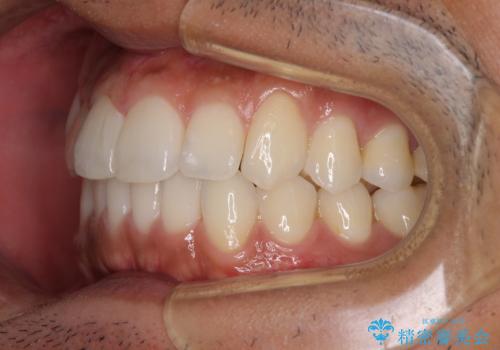

前歯のデコボコを治したい インビザライン矯正治療

- 前歯のデコボコを治したいとのことで来院された患者様です。

上下顎ともに歯列全体の後方移動とIPR(歯と歯の間を削る)によってデコボコが解消するように設計し、インビザラインにより治療を行うこととしました。

毎日22時間以上しっかりとマウスピースを装着していただいたので、スムーズに治療が進みました。歯と歯の間を削ることでうまくスペースコントロールでき、1年強で終えることができました。